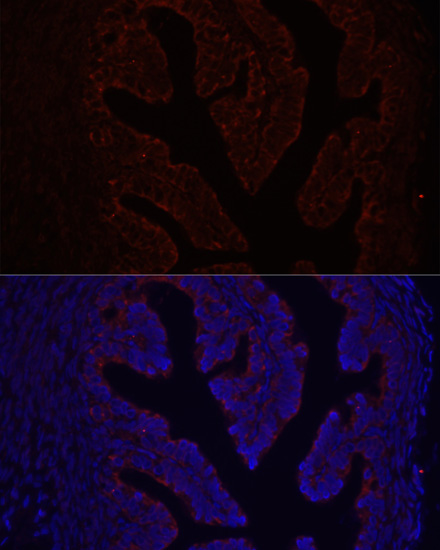

Immunohistochemistry of paraffin-embedded rat ovary using COL1A1 at dilution of 1:200 (40x lens).

Immunofluorescence analysis of rat ovary using COL1A1 at dilution of 1:100. Blue: DAPI for nuclear staining.